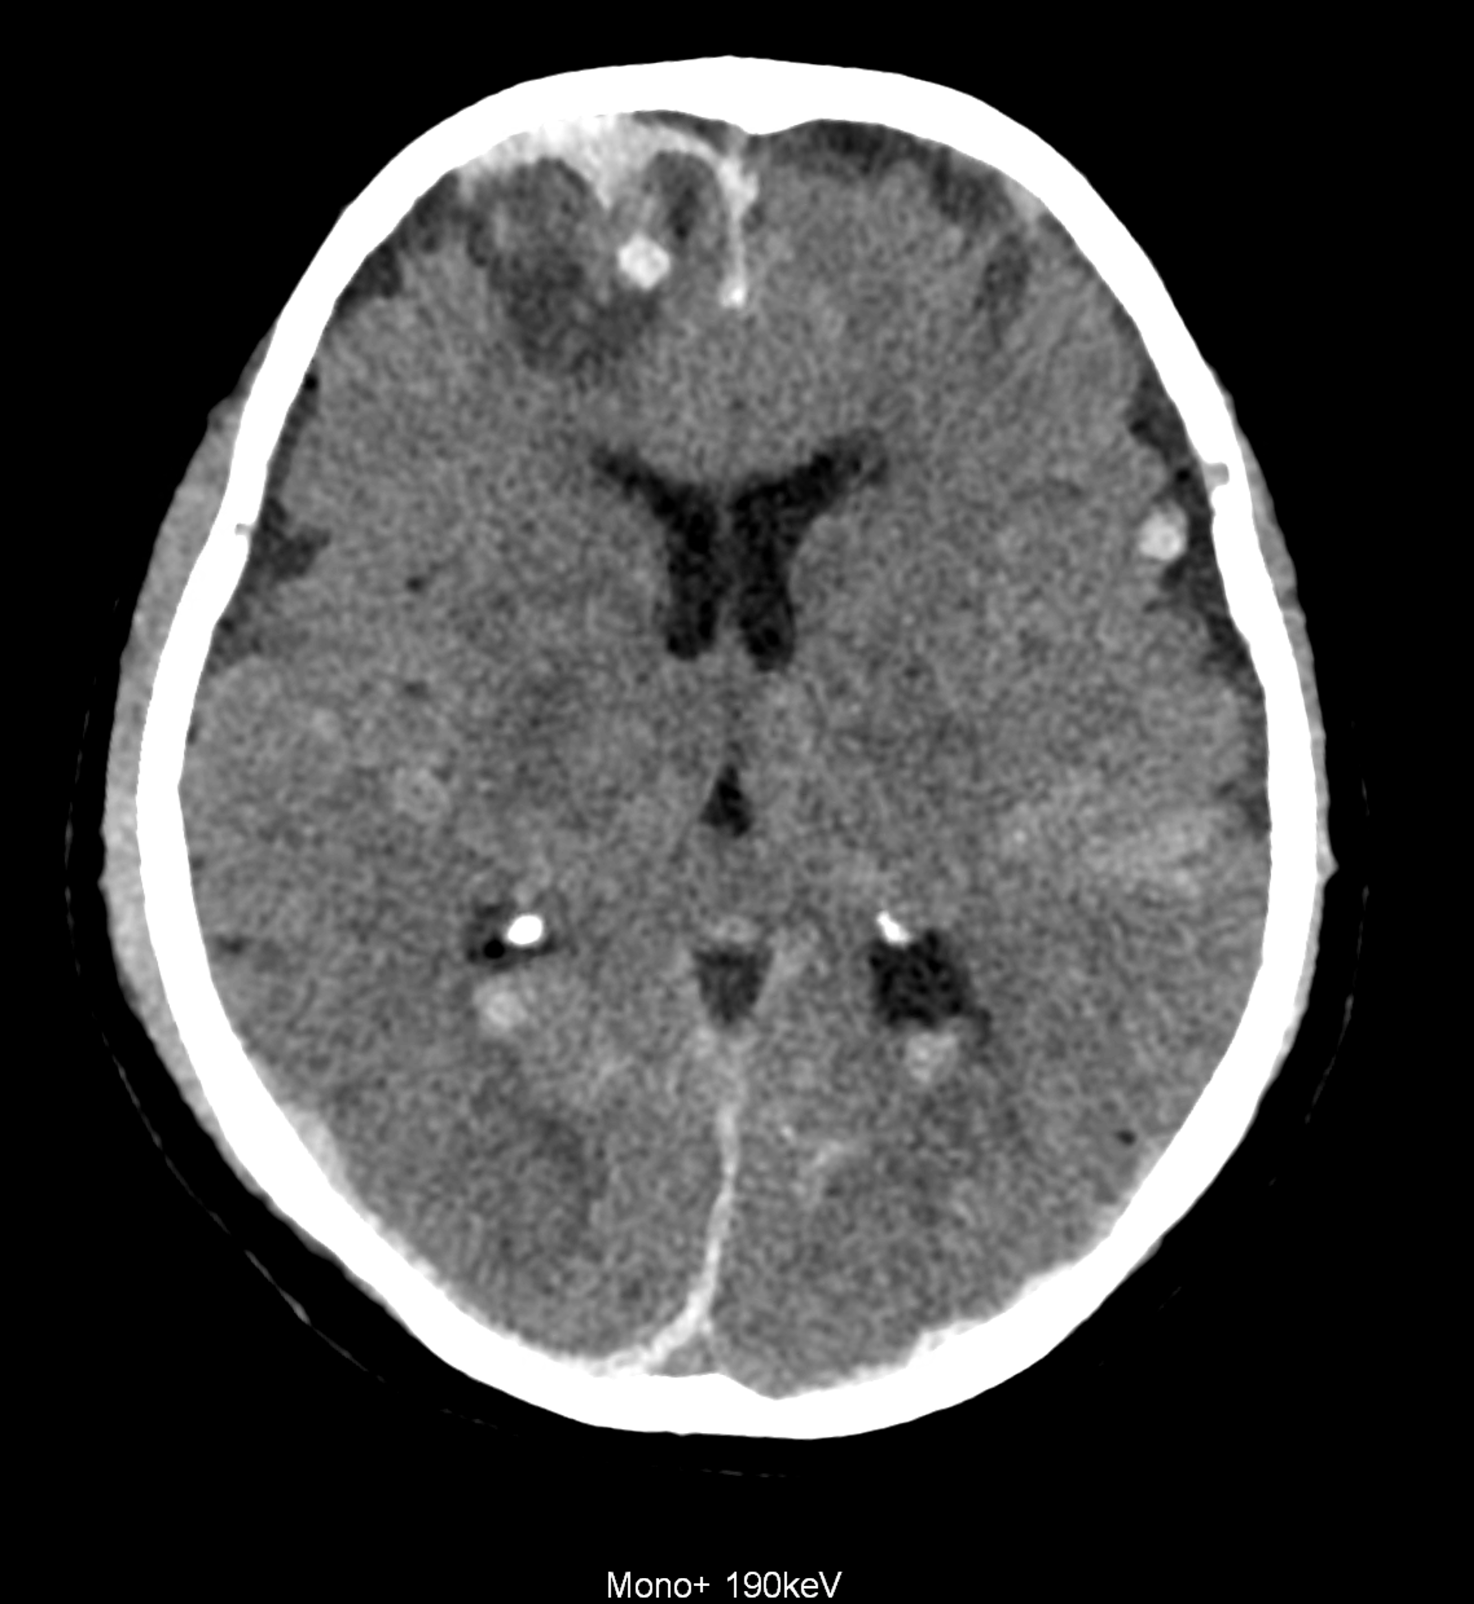

An example of the use of spectral imaging in complex brain injury, where contusions, diffuse axonal injury, subarachnoid hemorrhage, subdural hemorrhage, and blood in the ventricular system are present.

comparison of the images with the energies of monoenergetic reconstructions 40 keV, 67 keV (standard conventional reconstruction), 190 keV and virtual non contrast (VNC)

Bleeding is characterized by different absorption characteristics than healthy brain tissue (both gray and white matter) and cerebrospinal fluid. Due to the higher proportion of proteins with amino acids with disulfide bonds, the signal intensity increases at higher energies, making it possible to use monoenergetic imaging at energies above 140 keV, and/or virtual non-contrast. The hemorrhage then becomes more hyperdense, while the rest of the brain tissue acquires a uniform low signal. In addition to bleeding, areas of extracellular fluid of vasogenic origin are also imaged, i.e., in areas around contusion-type brain tissue injuries.